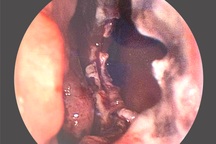

Ngày 25/2, Bệnh viện Đa khoa tỉnh Tiền Giang đã tiếp nhận nam bệnh nhân 68 tuổi bị hoại tử bộ phận sinh dục. Người này nhập viện trong tình trạng dương vật sưng to, bầm tím, gốc dương vật tổn thương, chảy máu.

Bác sĩ đang thăm khám cho nam bệnh nhân bị hoại tử dương vật (Ảnh: H.T.).

Sau khi thăm khám và xác định tình trạng tổn thương, các bác sĩ đã làm tiểu phẫu cho bệnh nhân, cắt bỏ chiếc nhẫn và xử lý khu vực da bị hoại tử. Dự kiến bệnh nhân sẽ được xuất viện trong vài ngày tới.